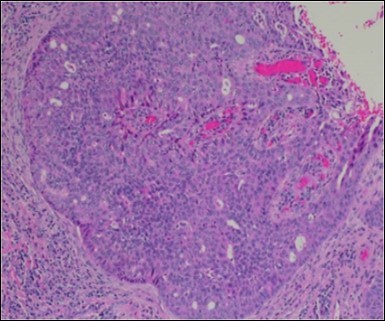

Figure 2.Epidermal projections lined with atypical and malignant epithelial cells in eccrine porocarcinoma (14).

Epidermal projections lined with atypical and malignant epithelial cells in eccrine porocarcinoma (14).

Classically, intra-epidermal and dermal nests of tumour cells exhibiting cellular atypia and enhanced mitotic activity are enunciated. Tumour aggregates articulate well demarcated, enlarged, atypical polygonal cells with indistinct cellular and nuclear outline, nuclear hyperchromasia , irregular nuclei, vesicular or prominent nucleoli and minimal eosinophilic cytoplasm. Polygonal tumour cells can depict central keratinisation 6, 7.

The neoplasm is composed of lobules of aberrant epithelial cells configured in cords with incrimination of the dermis and epidermis.. Malignant cells congregate within the epidermis or infiltrate the dermis, especially in the primary tumour. Tumour cells within tumour aggregates display a well demarcated cellular outline and appear distinct from encompassing squamous cells. Numerous tumour cell clusters demonstrate a cystic lumen. Prominent epidermal acanthosis is discerned on account of tumour cell proliferation 6, 7.

Granular arrangement of malignant cells and intercellular bridges are conspicuous with the demonstration of nuclear atypia, pleomorphism, prominent mitosis and tumour necrosis. A peripheral palisade is discernible within the cellular aggregates. Mitotic figures are common and can be quantified as up to 12 mitosis/ high power field. Tumour differentiation can prominently be of the ductal category with the demonstration of intra-cytoplasmic lumina. Comedo type tumour necrosis is evident along with foci of squamous differentiation The neoplasm is reactive to periodic acid Schiff ‘s (PAS) stain. (Figure 1, Figure 2, Figure 3, Figure 4, Figure 5, Figure 6, Figure 7, Figure 8, Figure 9, Figure 10, Figure 11, Figure 12, Figure 13.